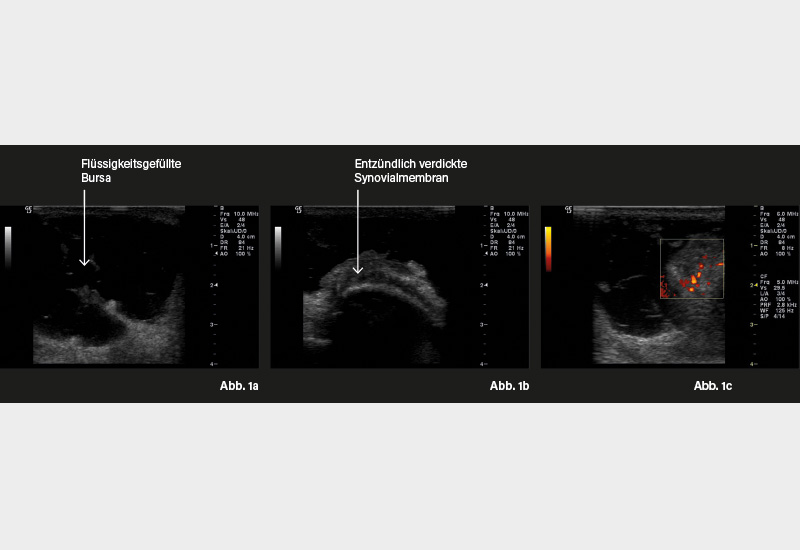

GELENK-/WEICHTEILSONOGRAFIE: Abb. 1a: Längsschnitt rechtes Ellenbogengelenk mit flüssigkeitsgefüllter Bursa, 1b: Querschnitt rechtes Ellenbogengelenk streckseitig mit entzündlich verdickter Synovialmembran, 1c: Längsschnitt rechtes Ellenbogengelenk streckseitig mit Powerdoppler und Nachweis einer Synovialitis Grad 2.

Die Diagnose ergibt sich in der Regel bereits aus der klinischen Untersuchung. Wenn keine traumatische Ursache vorliegt, ist die laborchemische Messung der Entzündungsparameter sowie der Harnsäure und Rheumafaktoren notwendig. Sonografisch zeigt sich eine erhöhte Flüssigkeitsansammlung und ggf. eine Proliferation der Synovialmembran. Weiterhin kann das Ellenbogengelenk mittels Röntgenuntersuchung in 2 Ebenen abgebildet werden.